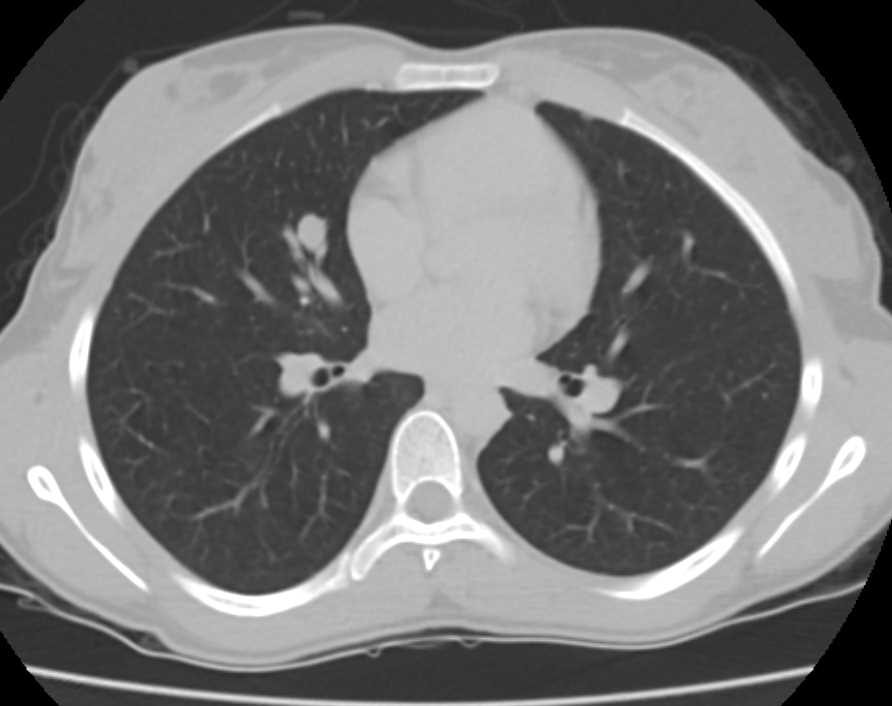

From www.ctisus.com

Metastatic Breast Cancer to Lung and Pleura Chest Case Studies CTisus CT Scanning Breast To Lung Cancer Prognosis Any stage 4 breast cancers that have metastasized to the lungs or other areas are more aggressive. The outlook for people with. About 60% of people diagnosed with metastatic breast cancer have lesions in either the lungs or the bones. If you’ve been told you have secondary breast cancer in the lung, you may want to know how long you’ve. Breast To Lung Cancer Prognosis.